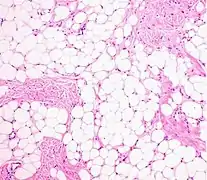

Histopathology of a lipoma: The mass is composed of lobules of mature white adipose tissue divided by fibrous septa containing thin-walled capillary-sized vessels.[23]